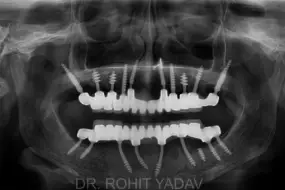

Replace all Teeth in the mouth for a Permanent beautiful Smile in 2-3 days

Patient will chew normal food in just 48 hours with very good long-term results

Patients with no bone/less bone benefit from Immediate loading implants with predictable long-term results